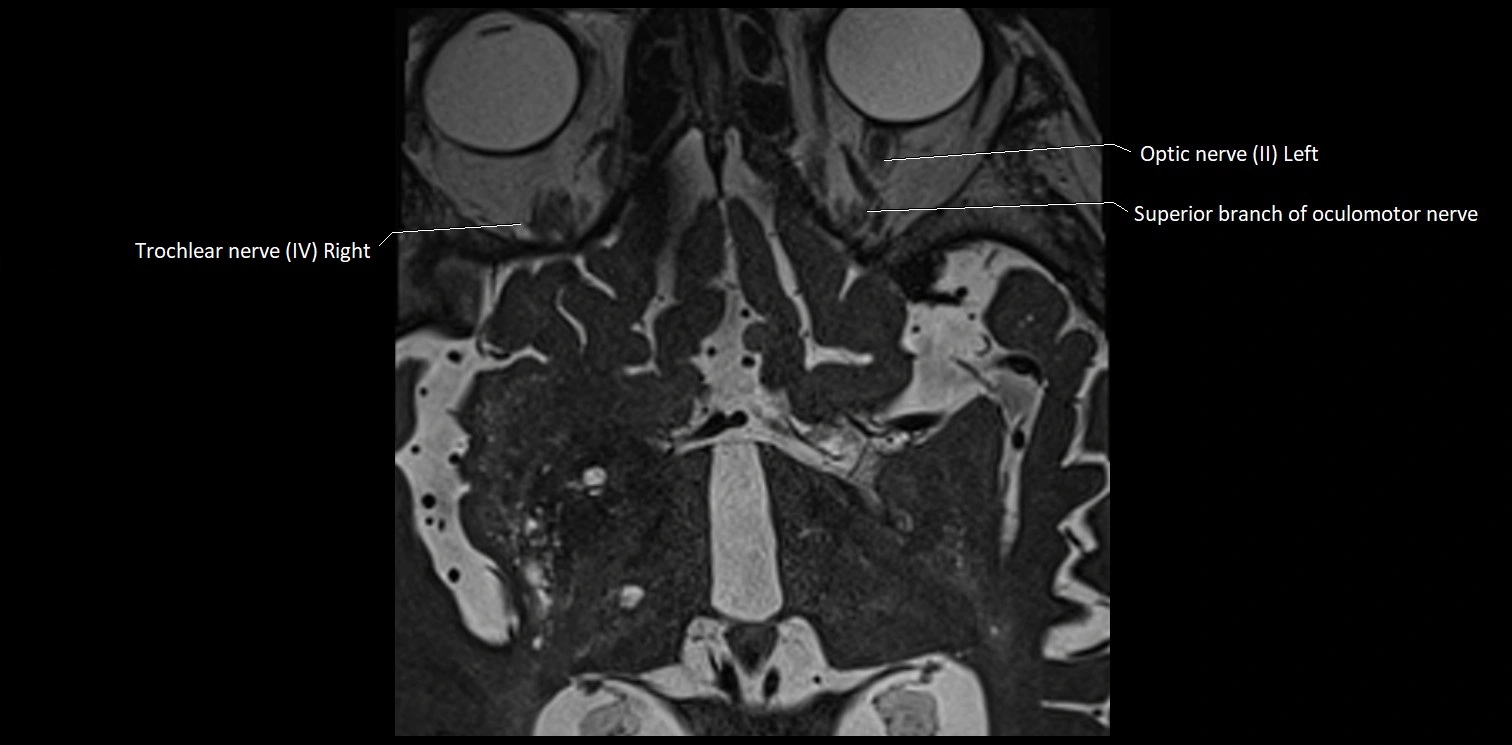

MRI images

image